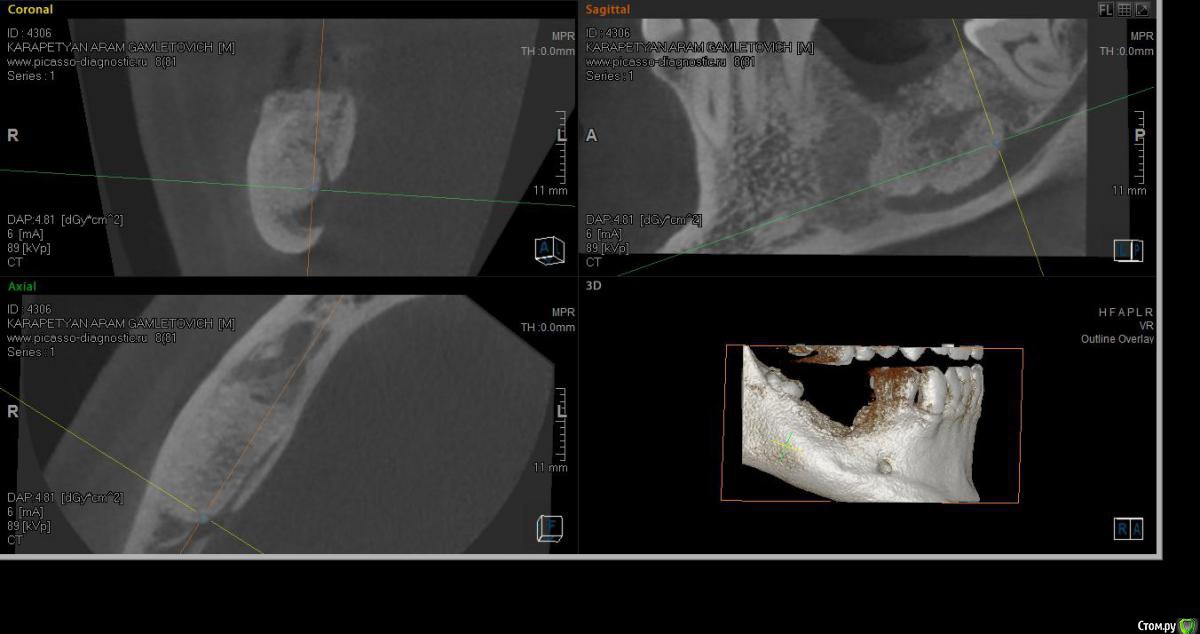

SashaDoc Опубликовано 14 сентября, 2015 Поделиться Опубликовано 14 сентября, 2015 (изменено) Коллеги, нужен совет. Со слов пациента, около 8 мес назад в Армении ему провели операцию по "удалению кисты" н/ч и "засыпали костный порошок" в объеме 6 гр. При мне пациент достал изо рта секвестр 10*5 мм, который он долгое время ощущал языком; во рту - небольшой (3*3мм) дефект слизистой, без отделяемого, в глубине зияет графт. Ничего не болит и не болело.На свежем кт картина не нравится, вопрос - что делать, куда направить? Пациент несколько в стомат теме и понимает, что что-то идет не так, тем более, что врач ему "обещал, что через пол года там кость будет" Изменено 14 сентября, 2015 пользователем SashaDoc Ссылка на комментарий